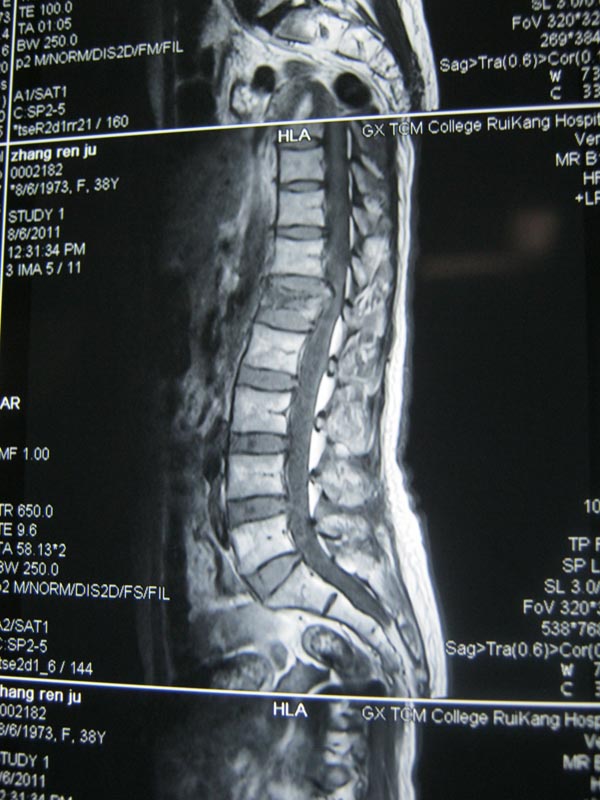

患者术前的磁共振片